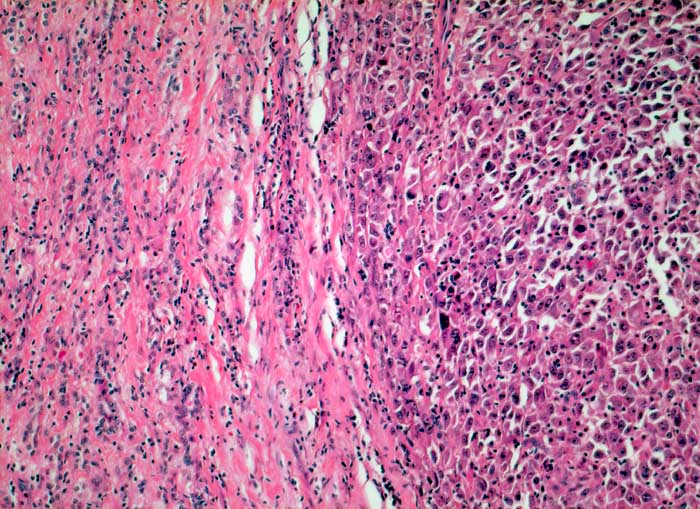

PathoPic ID 5457 - Anaplastisches Schilddrüsenkarzinom

Anaplastisches Schilddrüsenkarzinom

Anaplastischer solider Tumorknoten mit bizarren grossen Tumorzellen.

Strumaknoten links mit Einengung der Trachea

Histologie

100